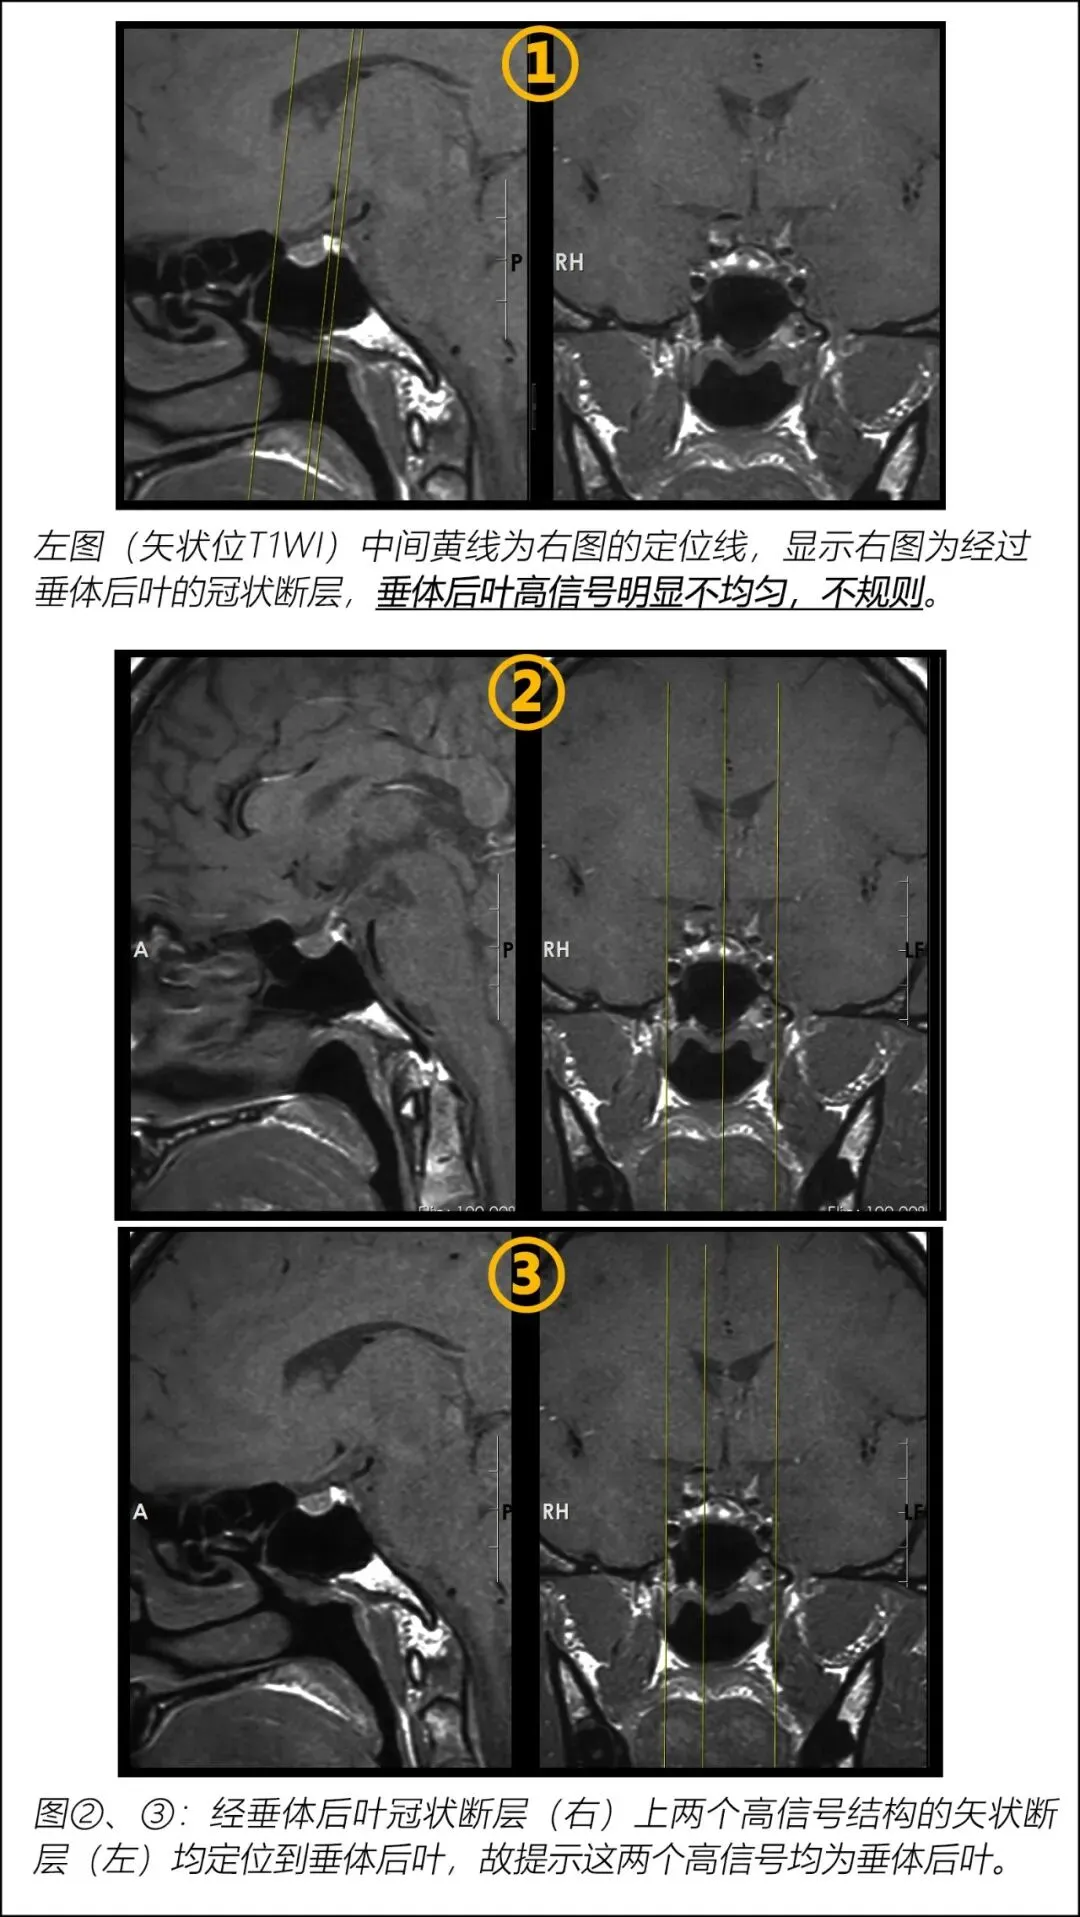

垂体后叶在矢状位上的典型表现:①紧贴鞍背;②规则前凸;均匀高信号。但实际上,并不是这么典型。

鞍背富含脂肪容易导致矢状位看不到垂体后叶的高信号。

实际上,并不总能看到紧贴鞍背、规则前凸及均匀高信号的垂体后叶,而是经常看到垂体后叶信号不均匀、前缘不规则。这可能提示神经分泌颗粒的不规则分布。下图为我门诊见到的一位患者,断层上看到垂体后叶高信号明显不规则。